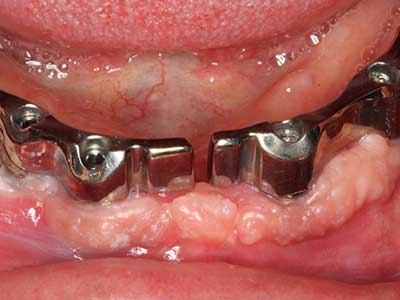

Indication: Periodontal therapy

Marginal periodontal diseases are the main reason for extractions in advanced age. These diseases are primarily caused by bacterial colonization of the gingival pocket, which causes inflammation followed by loss of the periodontium. The formation of subgingival biofilms and concrements is a significant aetiological factor for marginal bone atrophy, so their removal is an important part of the treatment (Drisko 2014, Plessas 2014).

Initial and surgical treatment phases are differentiated in the treatment of marginal periodontitis. In addition to instruction in oral hygiene and motivating patients, both phases should include adequate cleaning of the root surface. In the regenerative setting an open access is generally preferred. The root surface can be cleaned by piezosurgery using special attachments, where instruments with different curvatures are used to reach areas that are difficult to access, such as furcations. The integrated irrigation in the system flushes the detached concrements and bacteria out of the pocket. Specialized systems such as the Piezomed also include application feedback to minimize the ablation of hard dental substance. The greater the pressure on the periodontal attachment the greater the reduction in the amount of ablation.